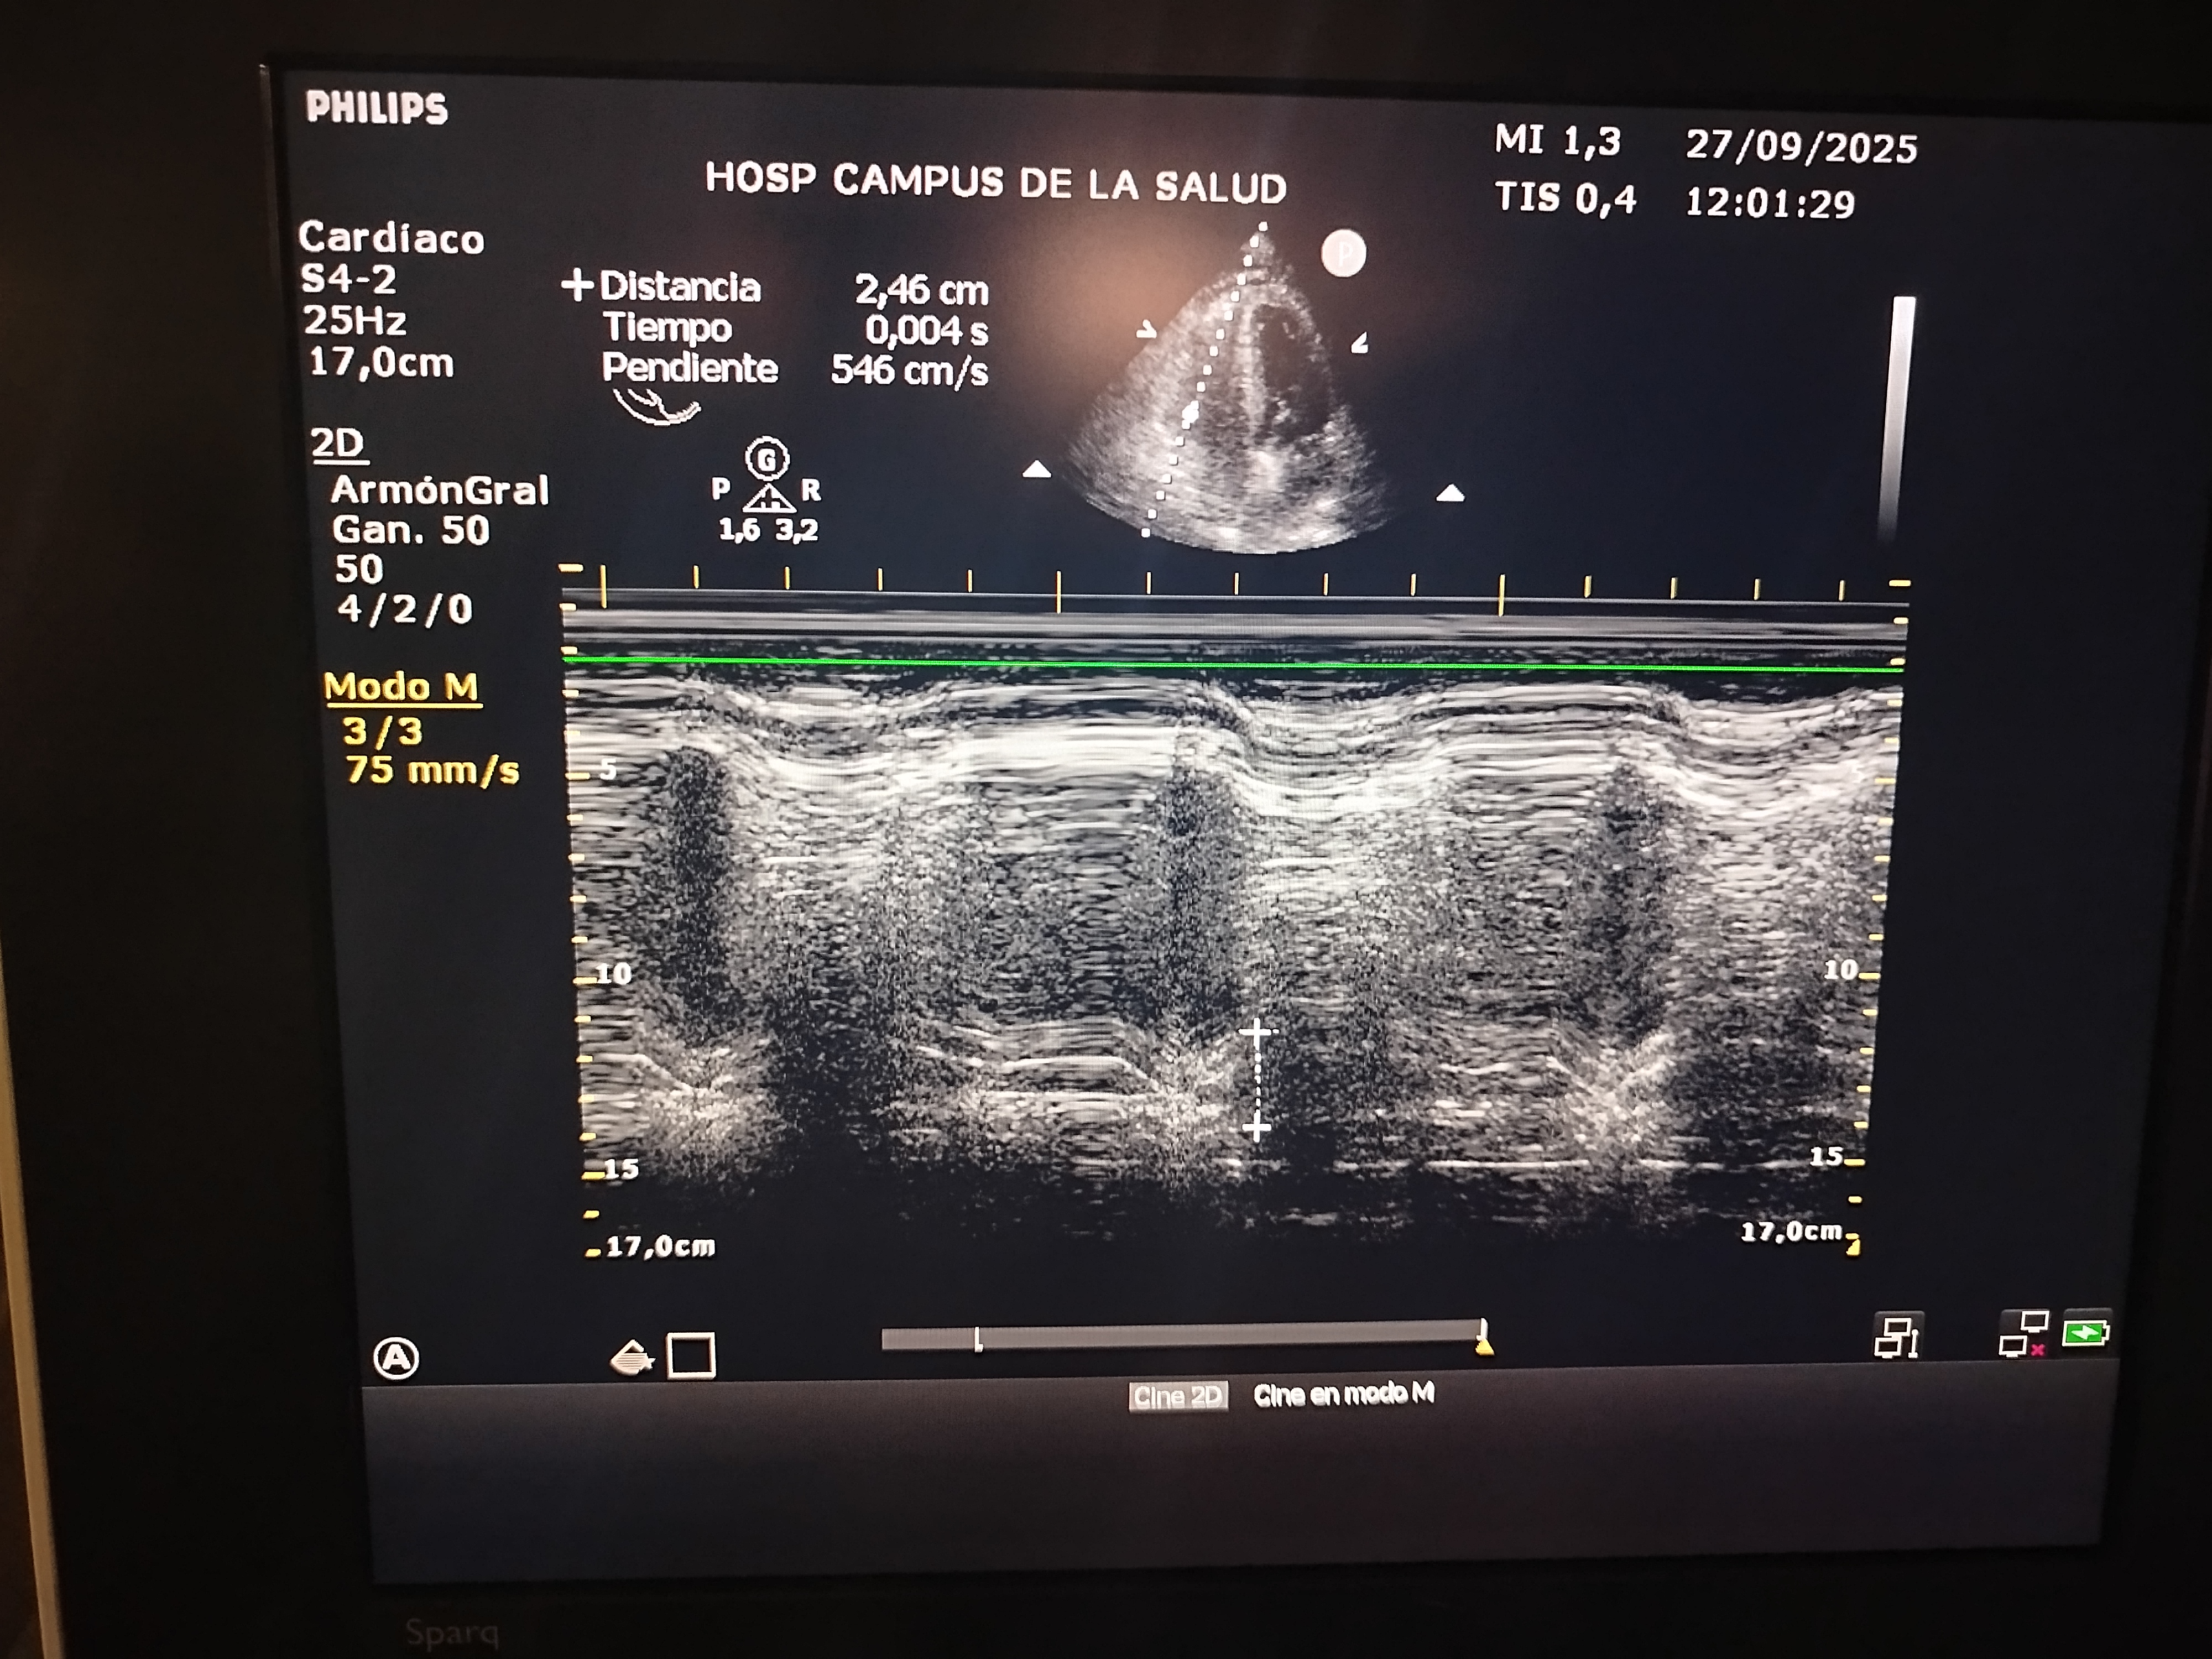

Diámetro VCI: 1.73

Colapso VCI: 10%